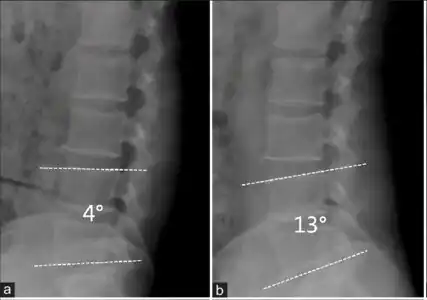

L5 S1 Spondylolisthesis Grade II with forward slipping of L5 on S1 <50% -